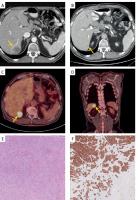

Figure 3

Imaging of the metastatic lesion and histopathological examination. A, B – Contrast-enhanced CT. Solitary hypovascular metastatic lesion between the 6th and 7th liver segments. A – before neoadjuvant treatment – lesion measuring 32 × 35 mm (yellow arrowhead). B – significant reduction of metastatic lesion to a size of 12 × 15 mm after neoadjuvant treatment (yellow arrowhead). C, D – 18F-FDG PET-CT. Solitary lesion between the 6th and 7th liver segments, with increased FDG uptake, consistent with a liver metastatic tumor (yellow arrowheads). E – Ampullary adenocarcinoma – liver metastasis. Liver parenchyma is visible in the lower right of the image. Original magnification: 10×. F – Ampullary adenocarcinoma – liver metastasis. Cytokeratin 7 expression. Original magnification: 10×